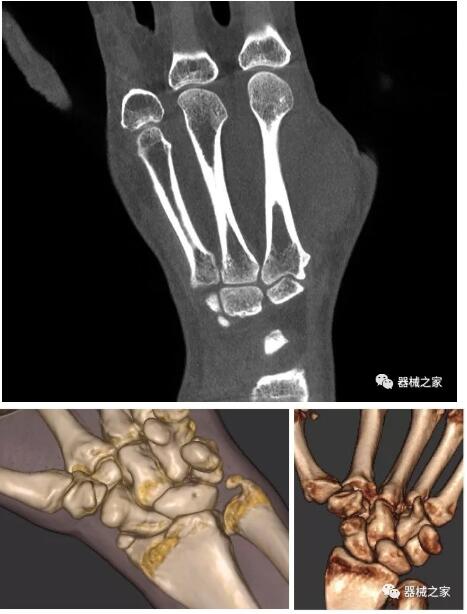

以上介紹的CT均來(lái)自國(guó)外同一家公司,這些CT均配置了可視化軟件,可以進(jìn)行切片、3D重建以及大型CT附帶的所有典型的操作功能。

以下是這些“特立獨(dú)行”的CT所拍出來(lái)的圖像: